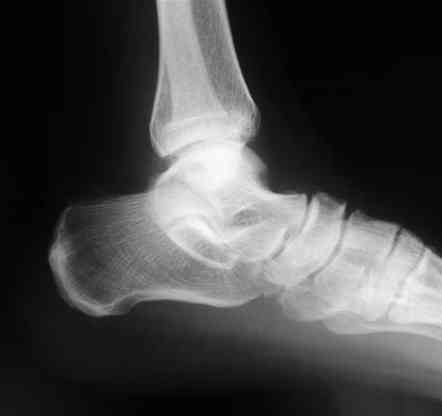

В приложении отправляю послеопер. снимки бедра и лодыжки обсуждаемого вчера больного.